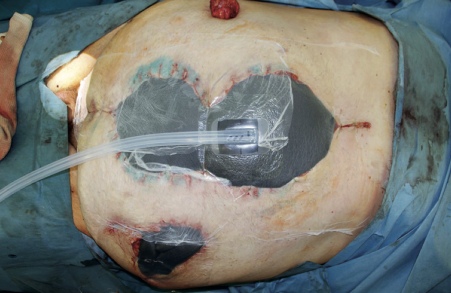

Одним из наиболее значимых достижений в лечении огнестрельных ранений живота последних лет стало внедрение методики вакуум-ассистированного закрытия брюшной полости (VAC-терапия). Данная технология позволяет эффективно удалять патологический экссудат, снижать микробную контаминацию, уменьшать отек тканей и создавать благоприятные условия для последующего окончательного закрытия лапаротомной раны.

В настоящее время применяются два основных варианта VAC-терапии брюшной полости: вакуум-ассистированная лапаростомия (ВАЛ) и вакуум-инстилляционная лапаростомия (ВИЛ). ВАЛ предполагает постоянное или циклическое воздействие отрицательного давления на брюшную полость через специальную губчатую повязку, покрытую адгезивной пленкой. ВИЛ дополняет этот принцип периодическим введением в брюшную полость раствора антисептика с последующей его аспирацией.

Сравнительный анализ эффективности двух методик, проведенный при лечении огнестрельного перитонита, показал, что применение ВИЛ сопровождается более низкой частотой формирования несформированных кишечных свищей по сравнению с ВАЛ: 2,4 % против 12,1 % (p=0,06). Кроме того, при ВИЛ отмечена более быстрая элиминация патогенной микрофлоры и менее выраженный адгезивный процесс в брюшной полости.

Результаты применения абдоминальной VAC-терапии на этапе Role 2 в ходе крупномасштабных боевых действий подтвердили ее высокую эффективность как метода временного закрытия брюшной полости после завершения I фазы DCS. Преимуществами методики являются: эффективное удаление патологического экссудата, возможность санации брюшной полости в процессе эвакуации на следующий этап, создание оптимальных условий для выполнения реконструктивных операций и окончательного закрытия брюшной полости в III фазе DCS.

Рис. 2. Окончательный вид установленной VAC-системы на лапаротомную рану

Исследование, включавшее 118 пациентов с огнестрельными повреждениями органов брюшной полости, осложненными распространенным перитонитом, продемонстрировало, что использование методик дренирования брюшной полости VAC-системами обеспечивало более быструю деконтаминацию при лечении огнестрельного перитонита, что позволяло сократить число программных санаций и снизить риск развития осложнений на 32 %. Важно отметить, что в данной серии наблюдений летальных исходов не было.